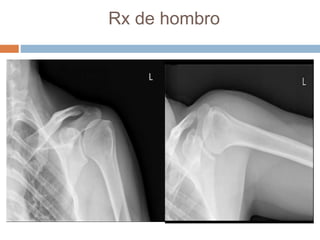

Este documento presenta el caso de un hombre de 37 años con dolor en el hombro izquierdo durante 7 meses. Las imágenes mostraron un nido tumoral en el hombro con características de osteoma osteoide. El osteoma osteoide es un tumor benigno que ocurre comúnmente en varones menores de 30 años y se caracteriza por un nido óseo y esclerosis reactiva. Fue tratado mediante excisión quirúrgica.